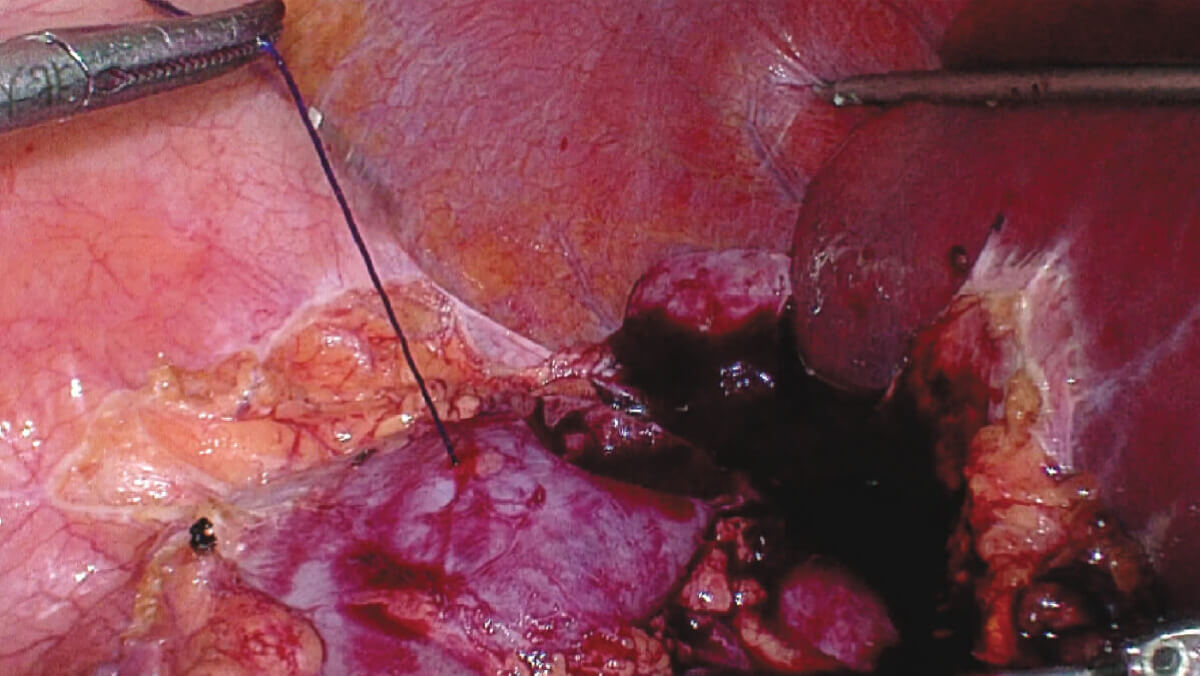

表面细节不遮盖

边界清晰,利于切缘评估

细微结构无伪影

避免术中误伤

荧光信号强弱分明

精准辅助临床决策

术中实时多维导航,领航诊疗一体新标准